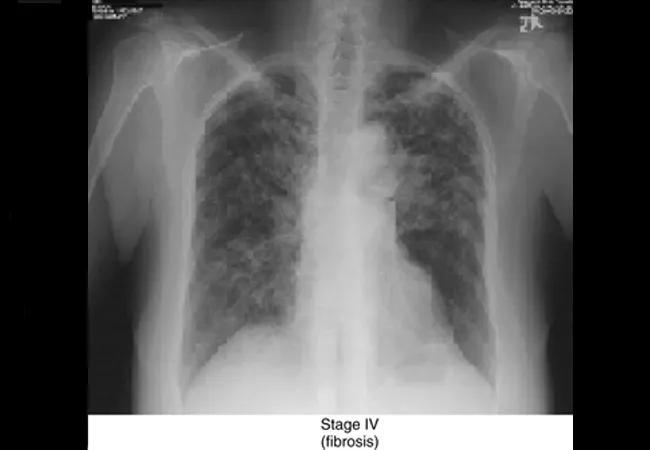

Image courtesy of Cleveland Clinic Center for Continuing Education.